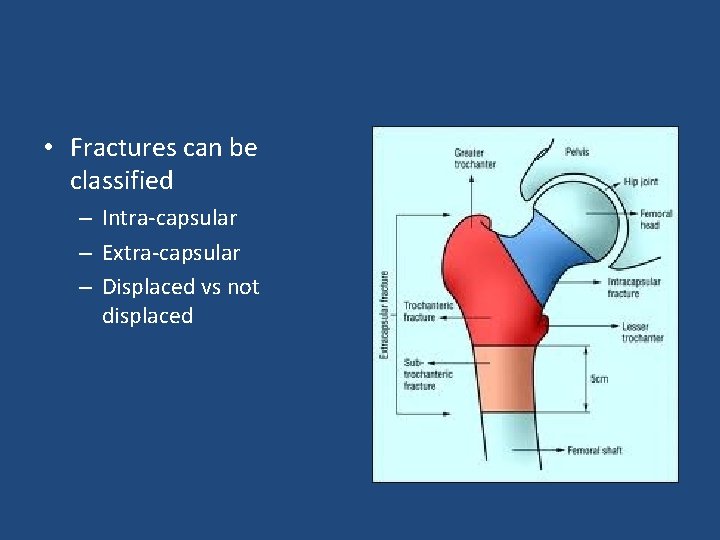

• Fractures can be classified – Intra-capsular – Extra-capsular – Displaced vs not displaced

• Intra-capsular: – Subcapital – Trans-cervical • Extra-capsular: – Basicervical – Intertrochanteric • AVN risk is higher with intra-capsular fracture.